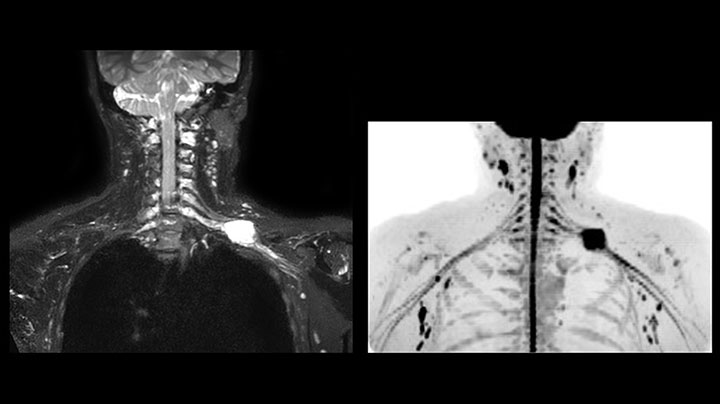

Obgleich die Region zwischen Hals und oberer Lungenspitze für ein MR-System einer der schwierigsten Bereiche ist, ergeben die mit Prodiva 1.5T erfassten Bilder bei diesem 56-jährigen Mann mit einem Pancoast-Tumor rechts eine gute Qualität. mDIXON TFE Bilder zeigen eine hervorragende Fettsuppression im Halsbereich und die diffusionsgewichtete Bildgebung enthält fast keine Verzerrungen.